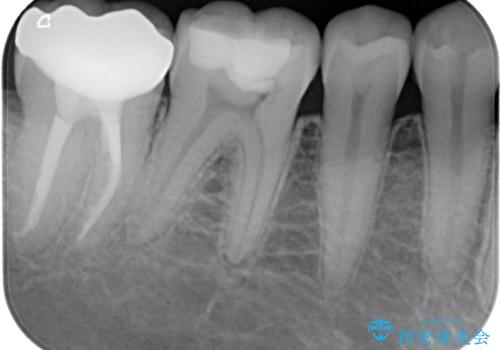

レントゲンやCTでは手前の歯の方が疑わしいように思えましたが、冷熱や電気刺激の反応から正常と判断されました。

最後の確認方法として、局所麻酔を行わずに最後臼歯の銀歯を外し、神経組織近くまで歯質を切削したところ痛みなどを全く感じず、その後無菌的環境下にて切削を進めたところ、神経組織の一部が壊死していることが確認されました。

その後は速やかに根管治療を行い、初回の処置以降は痛みや違和感が一気に引いたため、根管治療後にオールセラミッククラウンにて補綴治療を行うこととしました。